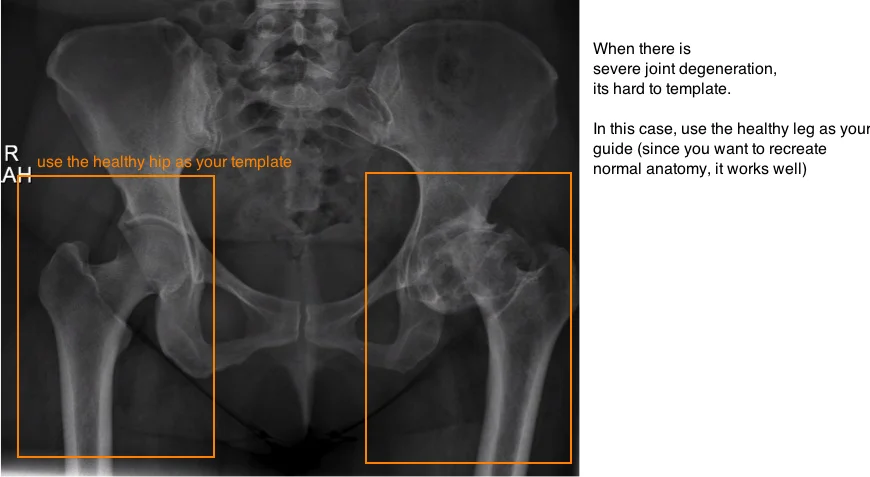

evaluate hip arthritis on xray hip degeneration on ap pelvis